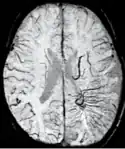

Stroke and hemorrhage

Diffusion weighted imaging offers a powerful means to detect acute stroke. Although it is well known that gradient echo imaging can detect hemorrhage, it is best detected with SWI. In the example shown here, the gradient echo image shows the region of likely cytotoxic edema whereas the SW image shows the likely localization of the stroke and the vascular territory affected (data acquired at 1.5 T).

The bright region in the gradient echo weighted image shows the area affected in this acute stroke example. The arrows in the SWI image may show the tissue at risk that has been affected by the stroke (A, B, C) and the location of the stroke itself (D). The reason that we are able to see the affected vascular territory could be because there is a reduced level of oxygen saturation in this tissue, suggesting that the flow to this region of the brain could be reduced post stroke. Another possible explanation is that there is an increase in local venous blood volume. In either case, this image suggests that the tissue associated with this vascular territory could be tissue at risk. Future stroke research will involve comparisons of perfusion weighted imaging and SWI to learn more about local flow and oxygen saturation.